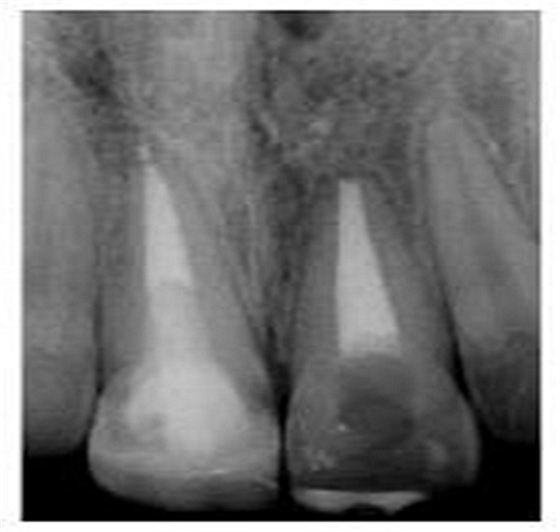

切端則采用透明樹(shù)脂,最后使用釉質(zhì)樹(shù)脂(Amaris, VOCO, Cuxhaven, Germany)。21的樹(shù)脂修復(fù)采用類似的方式。修復(fù)初步成型,拋光,恢復(fù)干燥牙釉質(zhì)的顏色。攝片顯示樁在根管內(nèi)位置合適(圖15)。最后一次復(fù)診精修、拋光充填體,完成治療。